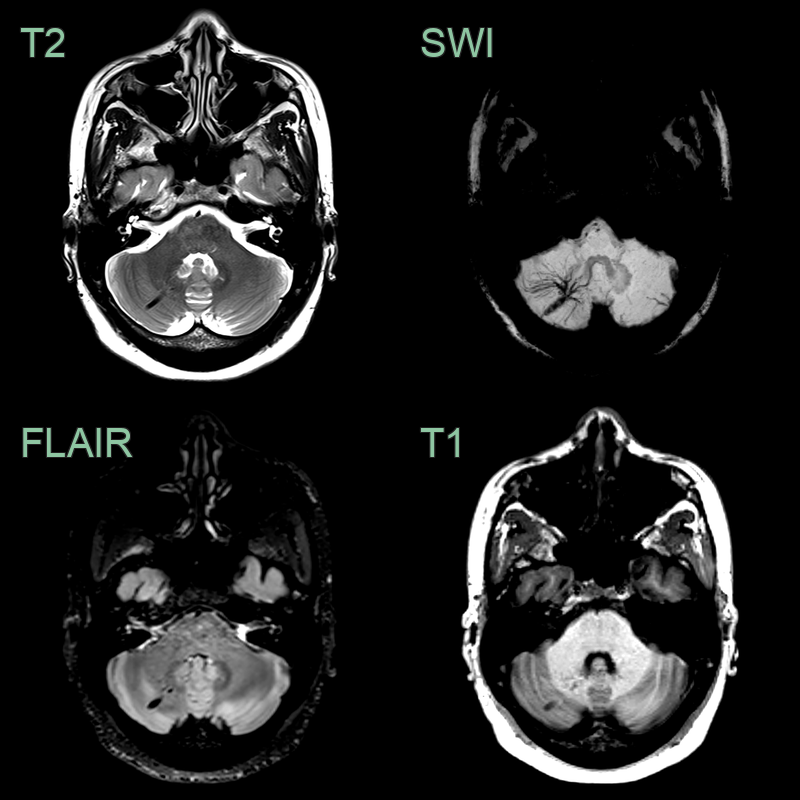

• Incidental findings of a dilated vein with the caput medusa sign.

• The DVA was associated with a small cavernoma (red arrow) .

• Incidental finding of a flow void on all sequences with a wider caput medusae on the SWI minimum intensity projection.